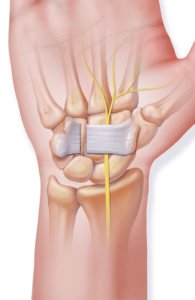

Operative Therapie: MPFL-Rekonstruktion

Bei ca 80% der ersten Kniescheibenluxationen kommt es zu einem Riss eines wichtigen Bandes, welches die Kniescheibe strecknah als einziger Stabilisator auf der Innenseite stabilisiert. Das sogenannte MPFL (Mediales patellofemorales Ligament) ist eine trapezförmige Struktur. Die Operation wird von uns mit einer minimalinvasiven Technik durchgeführt, bei der wir die Stabilität mit einer körpereigenen Sehne wiederherstellen. Die Sehne wird vom hinteren Oberschenkel entnommen und mit zwei kleinen Ankern an der Innenseite der Kniescheibe befestigt. Anschliessend wird unter Röntgenkontrolle der exakte Punkt am Oberschenkel festgelegt, an welchem das neue Band in jedem Winkelgrad die identische Spannung hat. Gerade diesem Operationsschritt wird oft zu wenig Bedeutung zugemessen, was wiederum zu einem erhöhten Anpressdruck der Kniescheibe und dauerhaften Schmerzen oder zu einer weiterhin bestehenden Instabilität führt. Die Befestigung hier erfolgt mit einer Schraube die der Körper in Knochen umbaut.